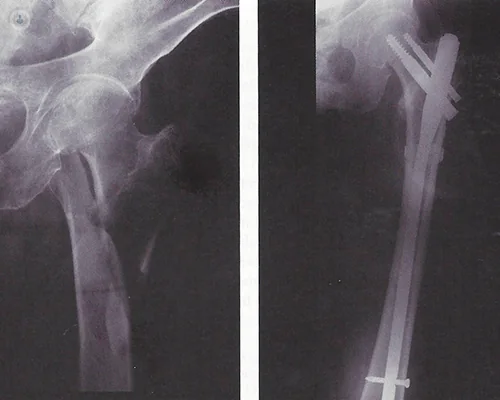

Esiti frattura anca / femore

Per esiti di frattura dell’anca/femore si intendono le conseguenze a breve o lungo termine dell’evento traumatico o dell’eventuale intervento chirurgico.

All’intervento possono seguire varie complicanze: il fallimento dell’osteo-sintesi, la mancata consolidazione della frattura, dismetria cioè la diversa lunghezza degli arti.

Può evidenziarsi un quadro clinico complesso con compromissione della normale funzionalità dell’anca, con dolore cronico residuo, limitazione dei movimenti che necessita dell’intervento dello specialista per limitare il danno residuo e ripristinare la funzionalità dell’anca.

Quando è necessario la sostituzione protesica

In base al quadro clinico e radiografico ed alle caratteristiche del paziente si valuterà se procedere a una nuova sintesi o ad un intervento di sostituzione protesica. In ogni caso si tratta di interventi complessi che vanno attentamente pianificati considerando varie opzioni di cura, ed eseguiti in strutture ad alta specialità.